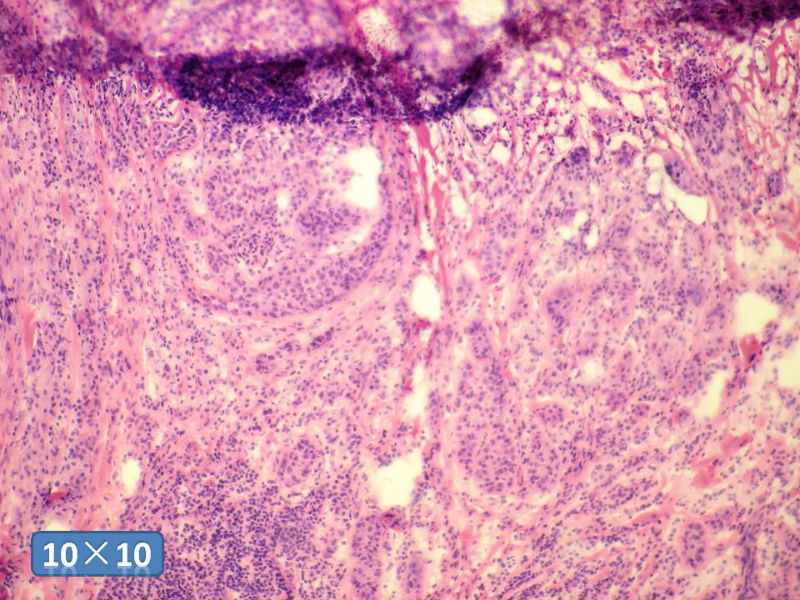

女性,50岁,乳腺肿物,冰冻切片(图1-25)

HE